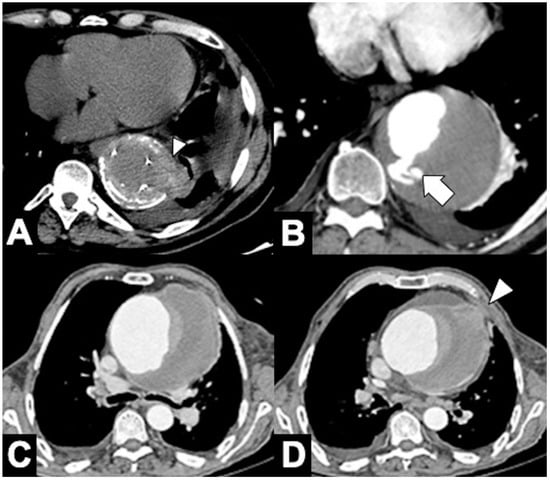

| › Ascending aorta involved (type A IMH). |

| › Aortic diameter > 5 cm (a greater stress on the dilated aortic wall implies a greater risk of rupture). |

| › Hematoma thickness (HT) > 11 mm. |

| › Luminal compression ratio (minimum/maximum transverse luminal diameters at the site of the maximal HT). |

| › Associated penetrating atherosclerotic ulcer (PAU) diameter > 20 mm and depth > 10 mm. |

| › Temporal aortic enlargement on serial imaging (rapid aortic diameter growth during hospital stay). |

| › Periaortic, pleural, or pericardial effusions, particularly if large or temporally progressive. |

| › Persistent pain or hemodynamic instability, or both. |